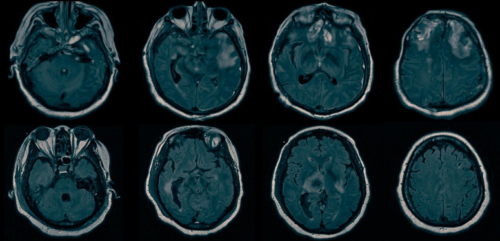

認知運動解離(cognitive-motor dissociation)